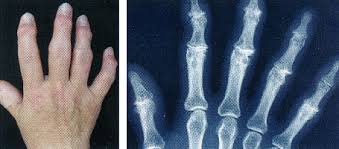

(1) 류마티스관절염

- 대표적인 자가면역 질환으로 손가락 마디를 포함한 다발성 관절에 대칭적으로 염증이 발생합니다.

- 초기에는 아침에 손이 뻣뻣하고, 통증과 부종이 나타나며 시간이 지날수록 관절 변형이 생길 수 있습니다.

(2) 골관절염(퇴행성 관절염)

- 나이가 들면서 관절 연골이 닳아 생기는 질환입니다.

- 주로 엄지손가락 관절이나 손끝 관절에서 통증이 시작되며, 관절이 딱딱하게 만져지기도 합니다.

- 헤버든결절, 부샤르결절 등의 형태로 나타날 수 있습니다.